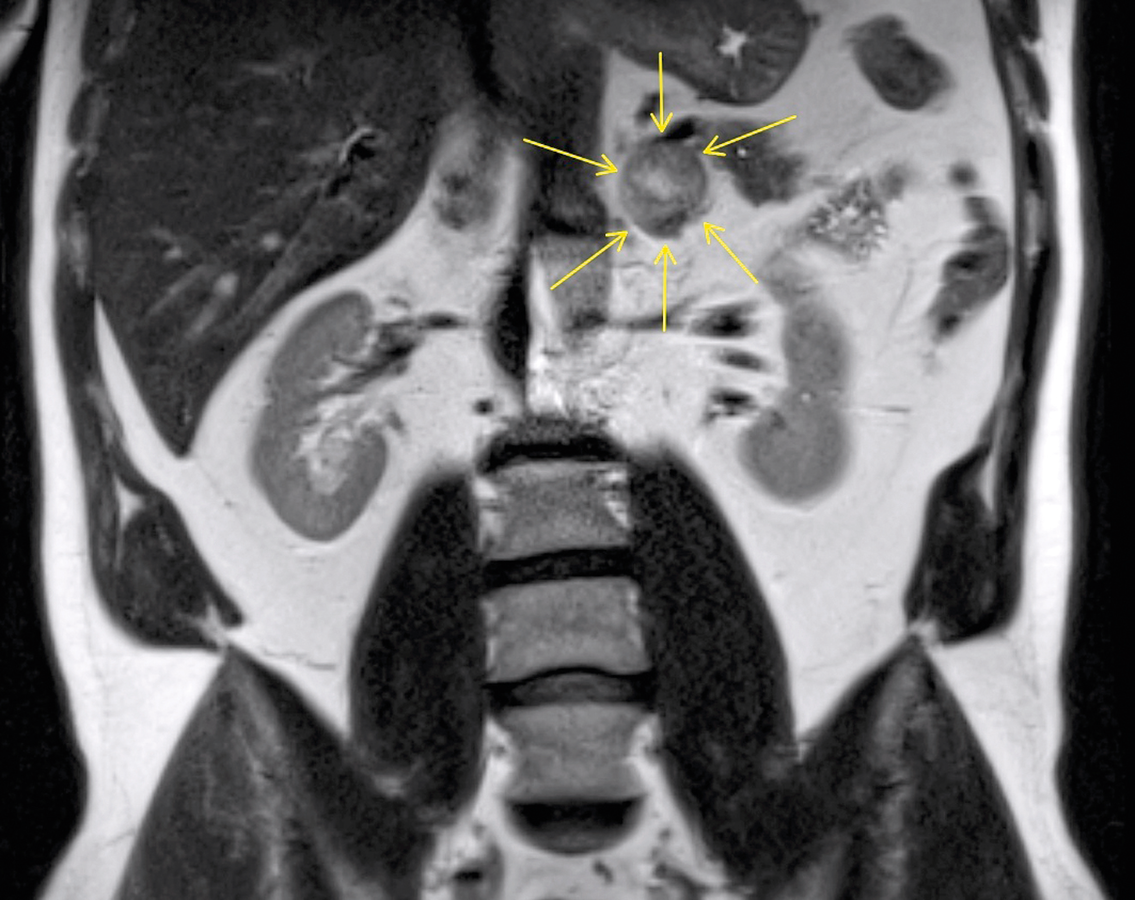

In der linken Nebenniere der Patientin fanden die Kollegen ein Phäochromozytom. Meist sind diese Tumoren gutartig. In der linken Nebenniere der Patientin fanden die Kollegen ein Phäochromozytom. Meist sind diese Tumoren gutartig. © Sundheimer C et al. Wehrmedizinische Monatsschrift 2018; 62: 404 © Beta Verlag & Marketinggesellschaft mbH, Bonn

Tatsächlich fiel im 24-h-Sammel­urin der Patientin eine Erhöhung von Normetanephrin auf. Ein daraufhin angefertigtes MRT offenbarte ein Phäochromozytom der linken Nebenniere. Als sich der Allgemeinzustand der Patientin einige Monate später verschlechterte und zusätzlich Synkopen auftraten, wurde der Tumor reseziert.

Phäochromozytom in der Nebenniere Phäochromozytom in der Nebenniere © Sundheimer C et al. Wehrmedizinische Monatsschrift 2018; 62: 404 © Beta Verlag & Marketinggesellschaft mbH, Bonn